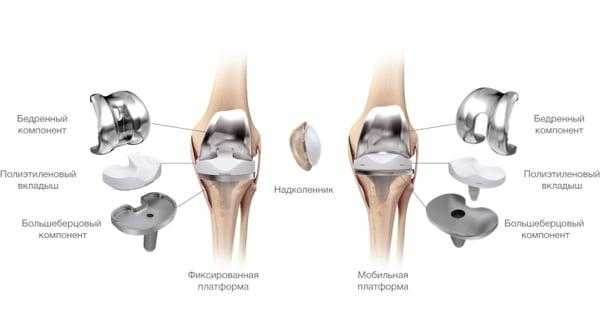

Протезные системы бывают с подвижной или неподвижной платформой, а также предусматривающие сохранение или удаление задней крестообразной связки. Различаются по виду фиксации, она может быть цементной, бесцементной и комбинированной.

- Подвижные и неподвижные платформы. Большинству пациентов ставят имплантат с амортизирующим вкладышем, который плотно связан с большеберцовым элементом, то есть изделия с неподвижной платформой. Наличие же мобильного вкладыша внутри металлического большеберцового компонента требует хорошего состояния мышечной системы и капсульно-связочного аппарата, в противном случае может произойти смещение протеза.